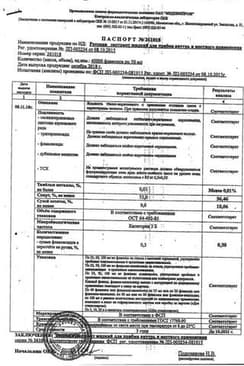

Ротокан экстр.для приема вн.и местн.прим.фл.50 мл 1 шт

Инструкция по применению Ротокан экстр.для приема вн.и местн.прим.фл.50 мл 1 шт

Общие характеристики

Срок годности

Сертификаты